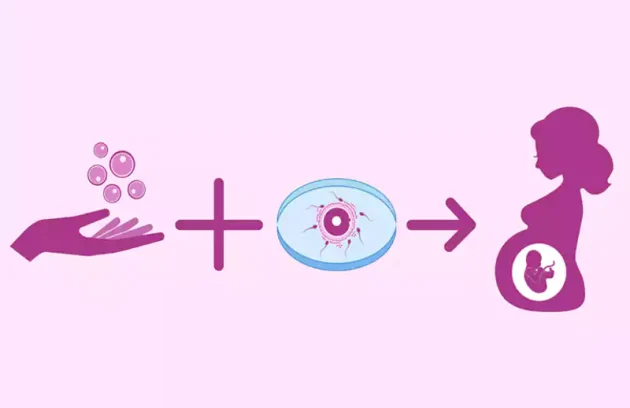

اهدا جنین

اهدای جنین اهدای جنین چیست؟ اهدای جنین نوعی تولید مثل ثالث است که در آن جنین حاصل از لقاح آزمایشگاهی یا آی وی…

تخمک اهدایی، راهکاری موثر برای درمان ناباروری زنان

تخمک اهدایی یکی از روش های موثر و تخصصی در درمان ناباروری است که برای بسیاری از زنان…